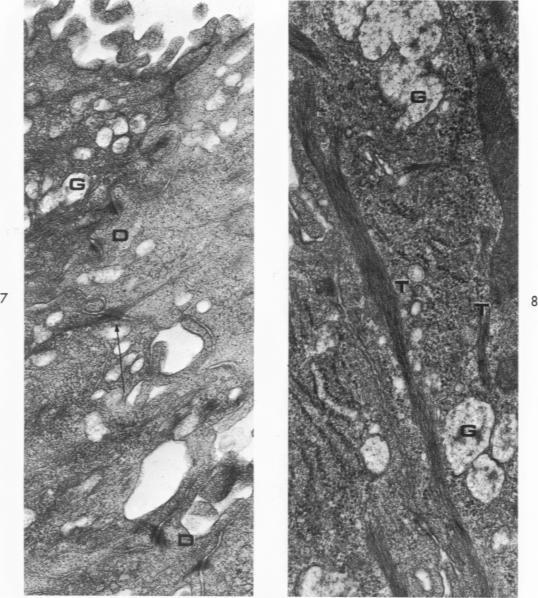

The major bronchi of swine, a dog and rabbits were examined with a scanning electron microscope and the fine structure of the openings of bronchial glands were studied three-dimensionally. The smallest areas of squamous metaplasia involved the duct openings. By examining serial sections with the light and transmission electron microscopes these early lesions were found localized at the opening of the bronchial gland duct. Cells intermediate to goblet and squamous cells were present in these lesions. Squamous metaplasia starting at this particular location is probably common and metaplasia can be an intracellular process.

用扫描电子显微镜检查了猪、狗和兔子的主支气管,并对支气管腺开口的精细结构进行了三维研究。鳞状化生面积最小的区域涉及导管开口。通过光学显微镜和透射电子显微镜检查连续切片,发现这些早期病变局限于支气管腺导管开口处。在这些病变中存在介于杯状细胞和鳞状细胞之间的细胞。从这个特定位置开始的鳞状化生可能很常见,并且化生可能是一个细胞内过程。